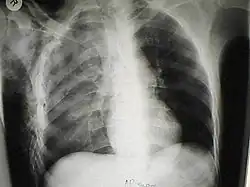

X-ray

Chest X-ray is the most common method used for diagnosis,[42] and may be used to confirm a diagnosis already made using clinical signs.[23] Consolidated areas appear white on an X-ray film.[47] Contusion is not typically restricted by the anatomical boundaries of the lobes or segments of the lung.[31][48][49] The X-ray appearance of pulmonary contusion is similar to that of aspiration,[36] and the presence of hemothorax or pneumothorax may obscure the contusion on a radiograph.[29] Signs of contusion that progress after 48 hours post-injury are likely to be actually due to aspiration, pneumonia, or ARDS.[13]

Although chest radiography is an important part of the diagnosis, it is often not sensitive enough to detect the condition early after the injury.[40] In a third of cases, pulmonary contusion is not visible on the first chest radiograph performed.[10] It takes an average of six hours for the characteristic white regions to show up on a chest X-ray, and the contusion may not become apparent for 48 hours.[10][31][48] When a pulmonary contusion is apparent in an X-ray, it suggests that the trauma to the chest was severe and that a CT scan might reveal other injuries that were missed with X-ray.[2]